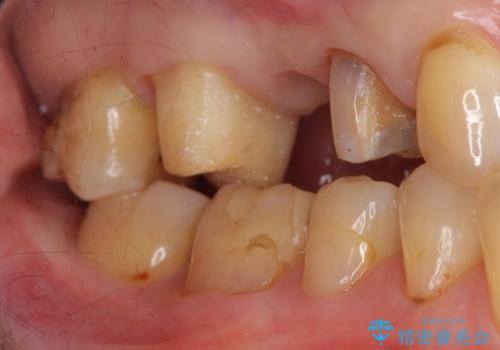

- 他院でブリッジの仮歯を入れたが、外れやすいため転院を希望された患者様です。

支台歯の形が角度が大きくついた形に形成してあり、外れやすい形になっていたため修正してから歯型をとりました。